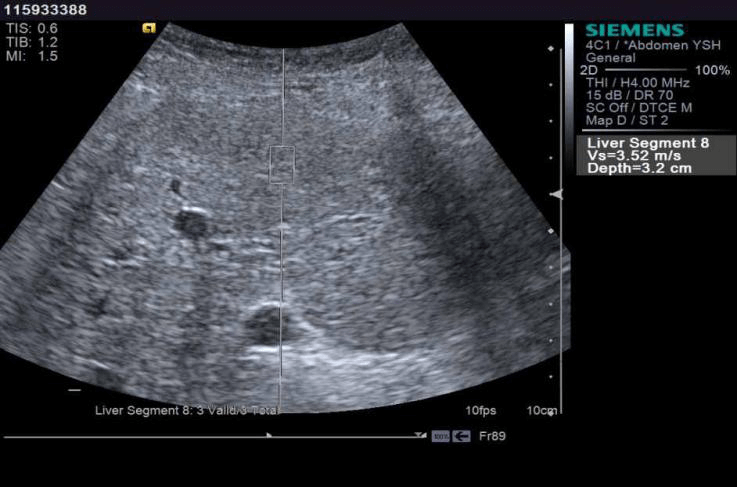

Shear wave or acoustic radiation force impulse (ARFI) from the transducer propagates in the tissue. Measurement of the propagation speed helps quantify the tissue stiffness in kilopascals or meters per second. Most important clinical use: quantitative assessment of liver stiffness. Multiple values are obtained over the right lobe of the liver and the median value is used as the index of stiffness.

Stiffer the liver, higher the recorded shear wave velocity. It is also applied in stiffness quantification in focal lesions and holds promise in stiffness imaging of spleen, kidneys and musculoskeletal system. Clinical indication for Liver Elastography:

- Evaluation of patients with unexplained portal hypertension (Normal liver stiffness in EHPVO, NCPF). Fibrosis cutoff values for US elastographic techniques are manufacturer dependent with normal values of stiffness being below 3 m/ s or 6-7 kpa and cutoff values for Cirrhosis ranging above 2.2 m/s or 15 kpa

Normal liver stiffness in a young male patient with portal hypertension. Elastography helped rule out cirrhosis